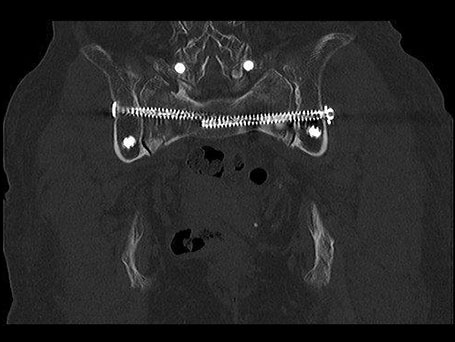

Hintere beiderseitige Kreuzbeinfraktur

Patientin mit beiderseitigem Bruch des Kreuzbeins und Querfraktur (U-Shaped fracture). Stabilisation über beiderseitige Verschraubung auf S1-Höhe sowie spinopelvine Stabilisation über Schrauben – Stabsystem führt zu einer Stabilisation des hinteren Beckenrings, sodass der Knochen im weiteren Verlauf trotz der Belastung heilen kann.

OPERATIVE VERSORGUNG DER PATIENTIN

Beiderseitige Verschraubung auf S1-Höhe sowie spinopelvine Stabilisation über Schrauben-Stabsystem